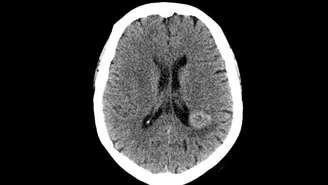

Vozes inexplicáveis salvaram mulher que tinha tumor na cabeça; entenda

Um caso de 1997 choca os cientistas até os dias atuais, pois mostra como nosso cérebro é misterioso e pode manifestar doenças físicas através de sintomas psicológicos

Primeiramente, tudo começou quando uma paciente de meia-idade, sem histórico psiquiátrico, passou a ouvir vozes nada familiares e persistentes. Essas pediam para ela procurar um médico e realizar um exame cerebral, isso porque afirmavam, calmamente, que ela tinha um tumor ali.

Quando contou isso aos especialistas, não recebeu atenção. Dessa forma, não quiseram que ela realizasse teste algum. Porém, as vozes continuaram, atestando que a investigação do caso era urgente. Então os médicos aceitaram a proposta para tranquilizá-la. E o resultado foi chocante. Descobriram que, realmente, ela tinha um meningioma, localizado exatamente no lugar apontado pelas mesmas.

Com isso, marcaram a cirurgia, que foi um sucesso, e, assim, o mais surpreedente aconteceu. Quando a mulher acordou do procedimento, escutou as vozes lhe dizendo: "Estamos satisfeitos que pudemos lhe ajudar. Adeus". E elas nunca mais apareceram desde então.